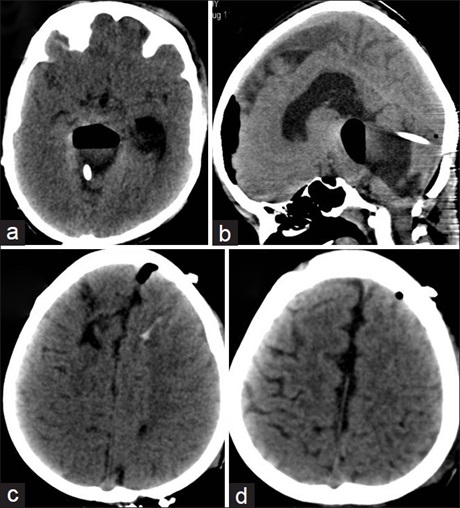

Hemispheric Multiple Fungal Brain Abscesses Due to Scedosporium apiospermum Following Surgery

Dr. Ravindra B Kamble, Mohan Rao Ravi, S. Raghavendra, Sreedharan Athmanathan (Author)

52-55

Views | PDF/EPUB Downloads : 251 / 0 / 25

DOI: https://doi.org/10.82235/wajr.vol22no1.287